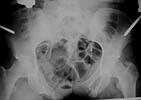

She now presents with a large bladder herniation (sorry, I have to reshoot the photo of the dramatic CT).

She has considerable pain in the pubic region and some pain posteriorly. She has burning pain in the left anterior lateral left thigh in the distribution of the anterolateral femoral cutaneous nerve---secondary to one of the exfix pin insertions. The anterior gap measures about 8 cm. Anterior fixation and bone grafting is planned. The question is: Can this big a gap be closed with just an anterior approach?

The Xrays and CT's provided show evidence of a Right sacral ala fracture, healed without significant vertical displacement or rotational abnormality. There is no evidence of external rotation through either of the SI joints. I see no evidence of there being a nonunion of a sacral fracture. I am unclear about the original purpose of the iliosacral fixation. Perhaps pre-op Xrays prior to this procedure would be helpful. In any event, there does not appear to be a substantial posterior pelvic ring deformity at this time. This is supported by the current AP pelvis which demonstrates well defined ilioischial lines bilaterally with a well positioned AP of the sacrum.

The anterior pelvic ring injury probably consisted of Bilateral superior and inferior ramus fractures as well as a fracture of the body of the pubis. The rami have united with the large anterior diastasis. I believe, therefore, that this is an isolated malunion of the anterior pelvic ring ocurring through 3 sites, the rami bilaterally and the body of the L pubis.